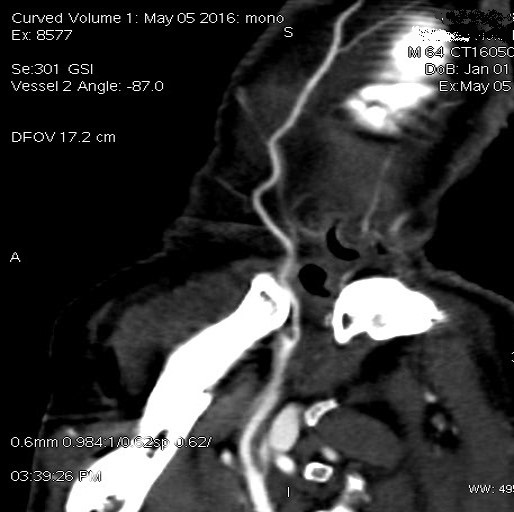

双侧颞浅血管状况及血管管径

双侧颞浅动脉在50keV显示清晰,远端分支良好。